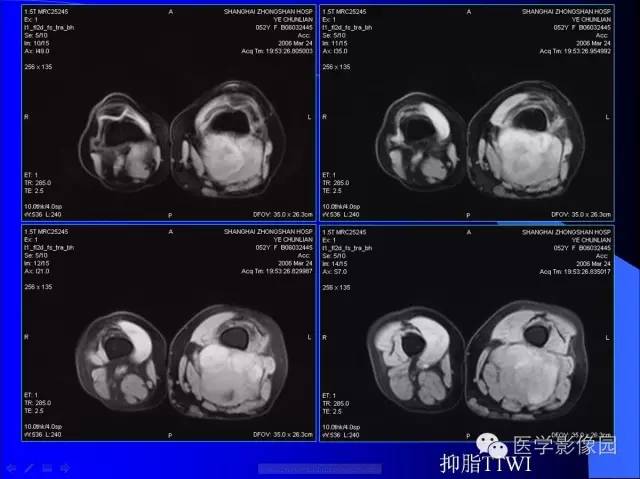

【病例】大腿恶性孤立性纤维瘤1例MR

病史:女,52岁,左大腿包块30年,逐渐长大。

孤立性纤维瘤起源于弥漫分布于人体结缔组织中CD34阳性的树突状间叶细胞。多见于头颈部、上呼吸道、腹腔和周围软组织。发病高峰40~ 60 岁, 女性多见。临床上多数病例表现为局部缓慢生长的无痛性包块。随着包块的增大, 会出现相应部位的压迫症状。孤立性纤维瘤多数病例临床上呈良性经过, 约10% 的非典型性和恶性孤立性纤维瘤局部复发率或远处转移率较高(80% )。